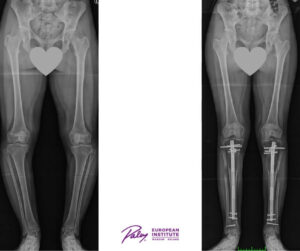

Lekarze i Pacjenci zgodnie twierdzą, że Precice pozwala na osiągnięcie wyższego poziomu satysfakcji Pacjenta poprzez podnoszenie jakości życia w okresie wydłużania kończyn. Metoda ta jest powtarzalna i w naszych rękach bezpieczna. W ciągu ostatniego roku uzyskaliśmy ponad 8 cm w przypadku kości u 16 pacjentów. Poniżej zdjęcie RTG jednego z nich.

Korekcja deformacji przy użyciu gwoździa PRECICE

W trakcie implantacji gwoździa bardzo często korygujemy również deformacje kończyn dolnych, na przykład szpotawość podudzi łącznie z uzyskaniem ponad 5 cm nowej kości.